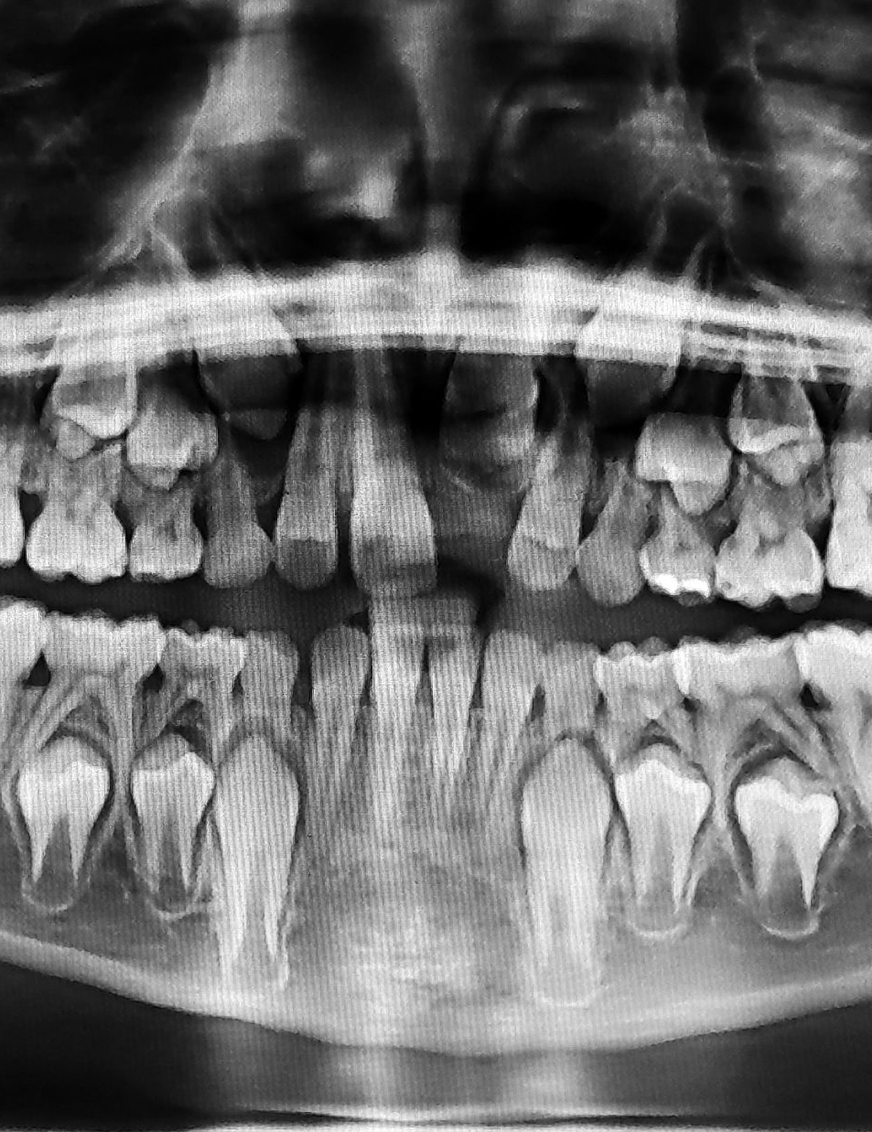

images